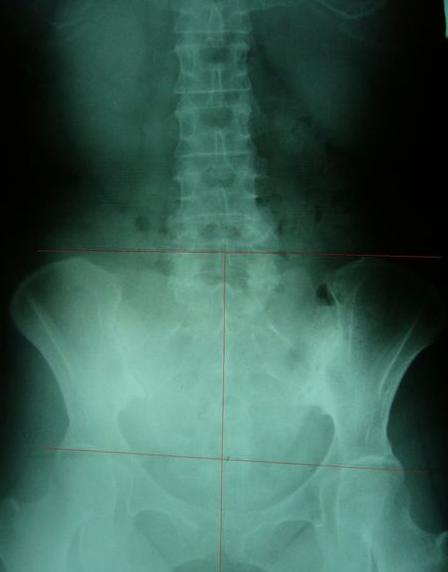

案例B:左图调理前骨盆严重歪斜左右极不对称 ;右图调理后骨盆歪斜改善骨盆圈显现对称心型圆弧